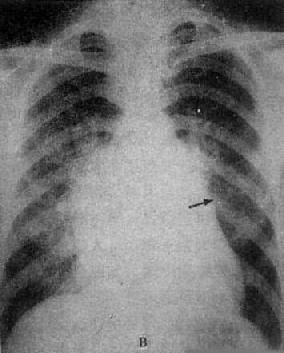

X线表现(图3-2-16),二尖瓣回流较轻,心代偿功能良好时,心大小和形状无明显改变,仅见左心房和左心室轻度增大,当二尖瓣回流在中度以上,心肌代偿功能较差时,则左心房明显增大,在心室也增大,透视下可见左心室收缩时因瓣膜关闭不全而左心房有强烈的搏动。肺有瘀血,右心室亦可增大。主动脉球正常或略小。

二尖瓣关闭不全并狭窄

图3-2-16 二尖瓣关闭不全并狭窄

心增大呈二尖瓣型,右心室增大,肺动脉

段突出,左心耳增大,有肺瘀血